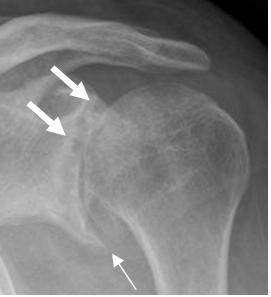

Presencia de osteofitos, disminución no uniforme del espacio articular, esclerosis ósea y quistes subcondrales. El compromiso es asimétrico. (Fig 161 A, 161 B y 161 C).

Fig 161 A. Artropatía degenerativa.

A: Rx AP. Cambios degenerativos con pérdida del espacio, formación de

osteofitos inferiores (Flecha delgada) y quistes subcondrales. (Flechas gruesas).